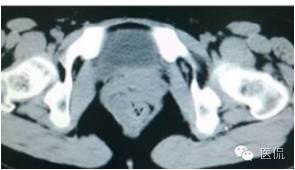

增强延迟期(CT值106HU)

结果

手术是:盆腔占位,病理为:血管肌纤维母细胞瘤。与肛门粘连,于是同时做了肛门的处理。